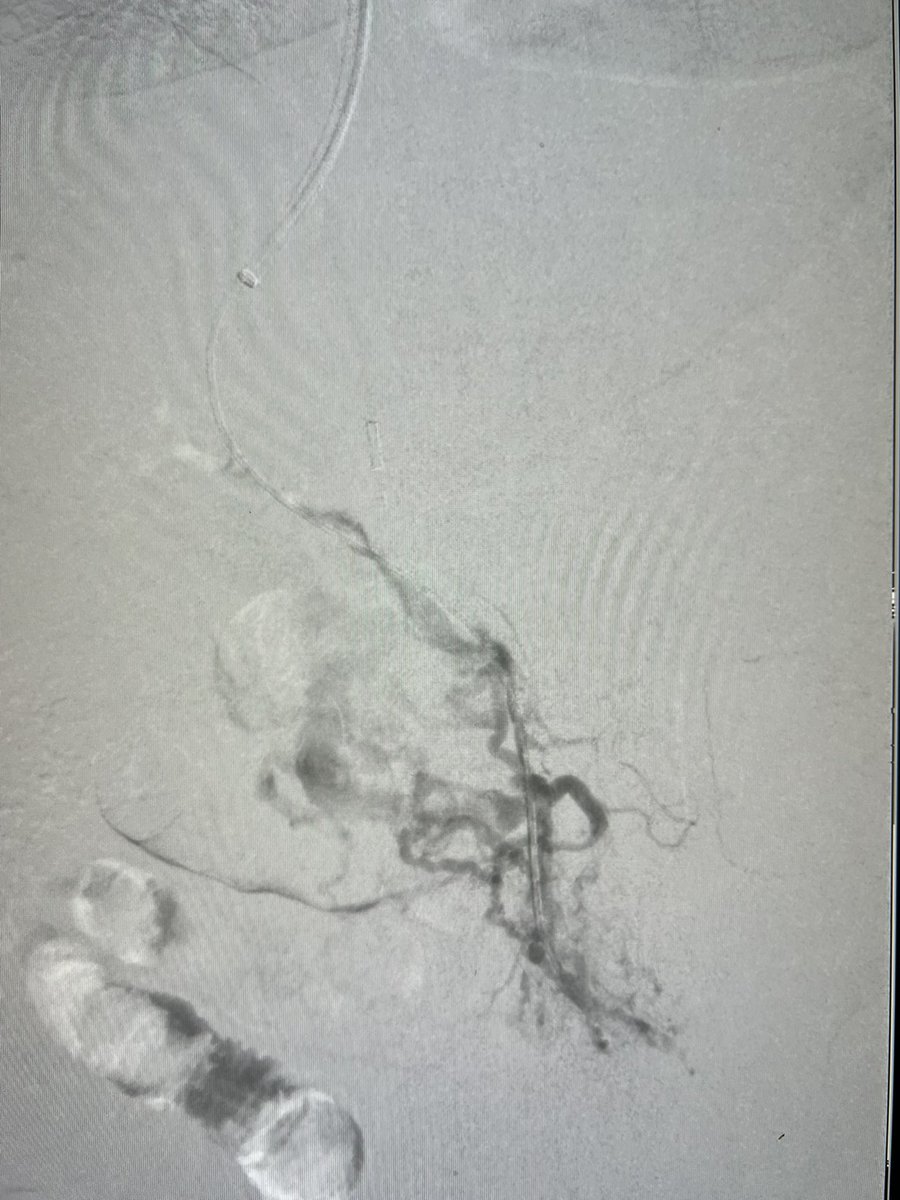

#MASLD #cirrhosis with GI bleeding, PVT not improving on heparin despite large acute component developed over 3 wks. ICE TIPS with subsequent asp vs thrombectomy established flow. #VIRad #GItwitter #livertwitter #meded #FOAMed

English